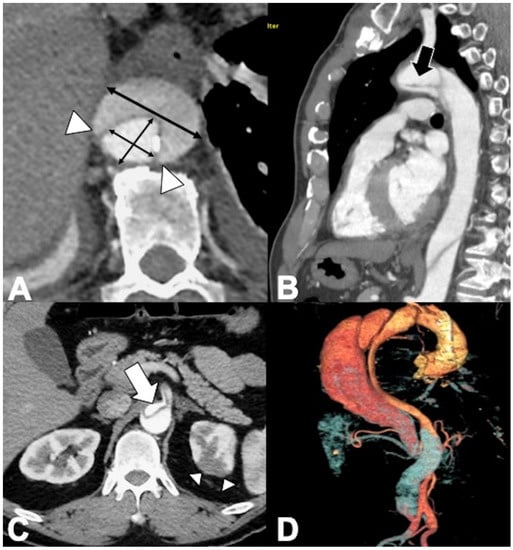

| › Ascending aorta involved (type A IMH). |

| › Aortic diameter > 5 cm (a greater stress on the dilated aortic wall implies a greater risk of rupture). |

| › Hematoma thickness (HT) > 11 mm. |

| › Luminal compression ratio (minimum/maximum transverse luminal diameters at the site of the maximal HT). |

| › Associated penetrating atherosclerotic ulcer (PAU) diameter > 20 mm and depth > 10 mm. |

| › Temporal aortic enlargement on serial imaging (rapid aortic diameter growth during hospital stay). |

| › Periaortic, pleural, or pericardial effusions, particularly if large or temporally progressive. |

| › Persistent pain or hemodynamic instability, or both. |